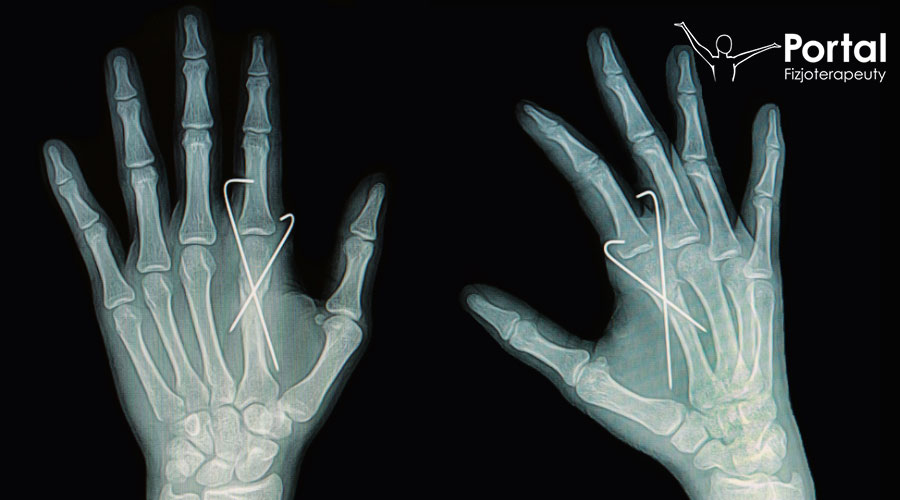

Druty Kirschnera są elementem aparatu Ilizarowa, który stanowi typ okrężnego stabilizatora zewnętrznego mocowanego na kości. Mają one średnicę od 1,5